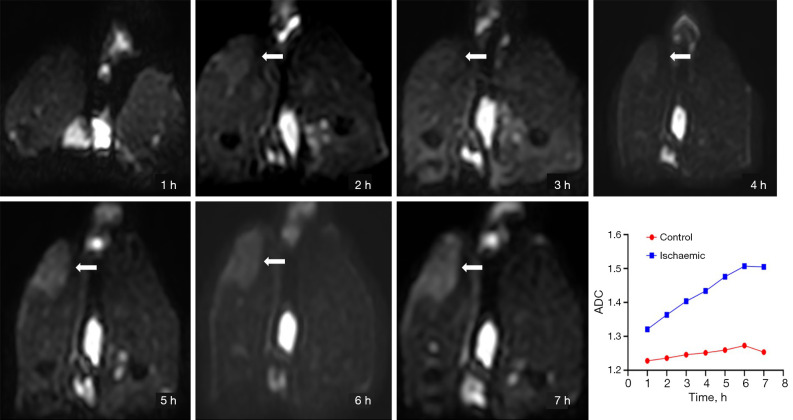

Results: The perfusion fraction (f) of ischemic muscle significantly decreased from 6.19%±1.13% at 1 hour to 2.50%±0.64% at 7 hours (control: 7.19%±1.03%), representing a strong negative correlation with ischemic duration (r=-0.790). The true diffusion coefficient (D) remained relatively stable [(1.41-1.46)×10-3 mm2/s] but was slightly elevated compared to controls. The pseudo-diffusion coefficient (D*) showed a sharp increase at 5 hours [(74.01±5.79)×10-3 mm2/s]; control: [(61.28±9.31)×10-3 mm2/s], followed by a drop at 6 hours [(59.44±15.77)×10-3 mm2/s], suggesting sudden structural changes, which were confirmed by histopathology. T2WI-FS and DWI showed increased signal intensity in ischemic muscle, with the T2 relaxation times being significantly elevated (P<0.001) and positively correlated with ischemic duration (r=0.807). Apparent diffusion coefficient (ADC) values also increased with time (r=0.623). The amide proton transfer effect was enhanced in ischemic skeletal muscle throughout the 2-7-hour post-ischemic period (ischemic: 2.26%±0.39% at the 7th hour vs. control: 1.77%±0.33%; P<0.05).